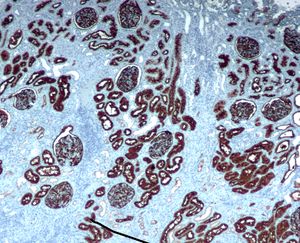

Immunohistochemical staining of normal kidney with CD10.